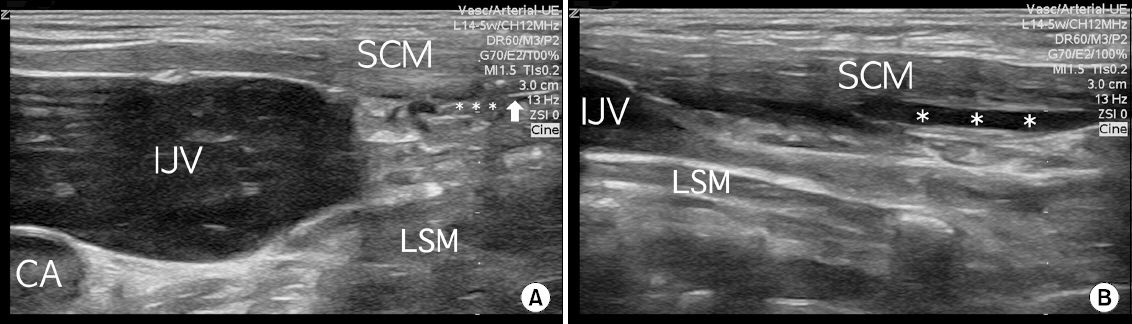

- A 70-year-old woman with an infectious thrombus in her left internal jugular vein (IJV) underwent carotid endarterectomy for stenosis and a highly movable plaque in her right carotid artery. She had been treated with antibiotics for four weeks before surgery due to Lemierre syndrome, a rare septic thrombophlebitis in the IJV secondary to an oropharyngeal infection. The right IJV was in a two-fold dilated state due to compensation for a thrombotic left IJV. Accordingly, superficial cervical plexus block was performed under ultrasound guidance to ensure safety and accuracy. During surgery, the alertness was maintained and the patient did not complain of pain in the absence of additional analgesics. No block-related complications were encountered. The authors report for the first time their regional anesthetic experiences in a patient with Lemierre syndrome.